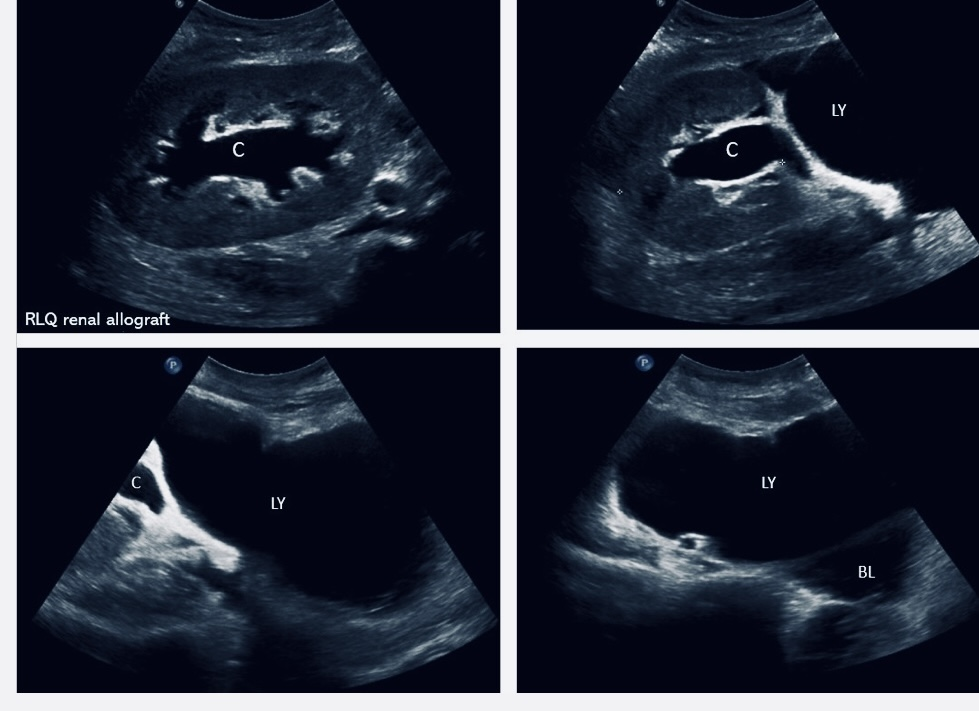

24 year female 3 weeks post renal transplant developed mild graft dysfunction and low grade fever. Imaging showed a large collection abutting the transplant ureter both anteriorly and posteriorly, pig tail insertion was done. Drain output was more than 3 litres per day.

56 year old male developed abdominal distension and pain 4 days after renal transplant. Drain output was more than half a litre per day.

53 year old male 15 days post renal transplant presented with graft dysfunction. USG revealed collection near lower pole of the kidney with mild hydroureteronephrosis. Drain output was 110 ml.

All 3 cases were treated with 20 mg of intra muscular octreotide. There was significant decrease in drain output with radiological shrinkage in the size and there was no recurrence of lymphocele on follow up.